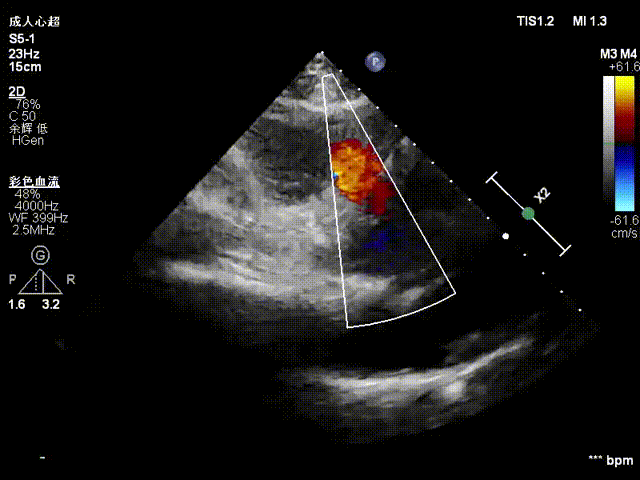

术前超声

术后超声